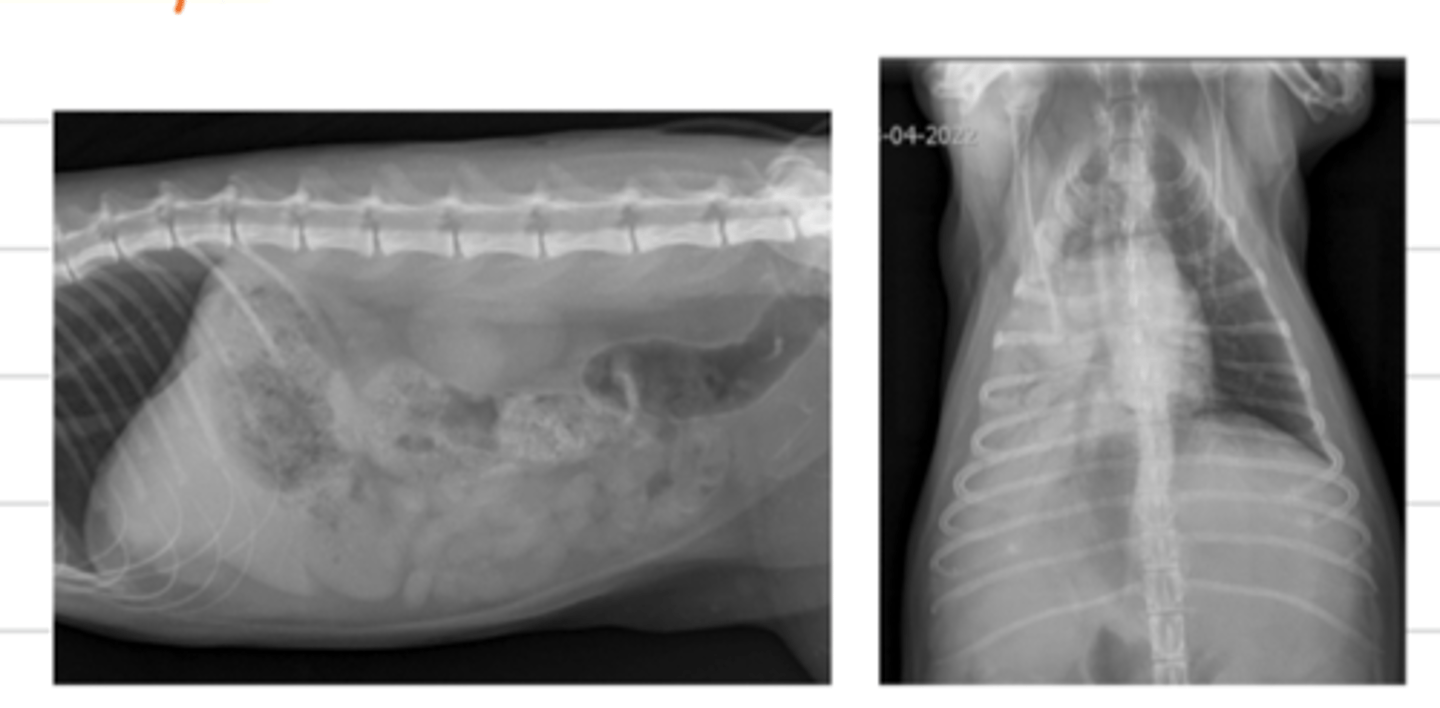

what are the 5 opacities of a radiograph, from most radioluscent to most radiopaque?

1. air

2. fat

3. soft tissue and fluid

4. mineral (bone)

5. metal

what are the 5 opacities of a radiograph?